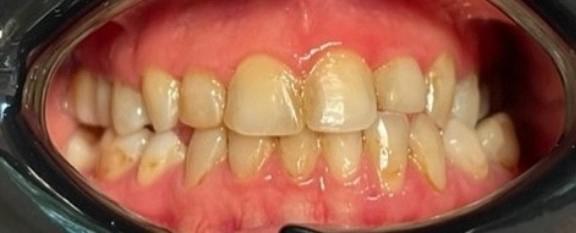

Ortodontzia ikusezina, zuritzea eta injektatutako karelak